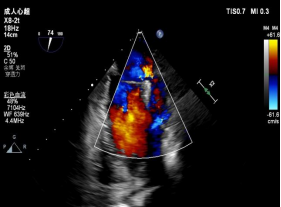

在浙大二院王建安教授、刘先宝教授的指导下,修建成团队携手我院麻醉科、心外科等科室如期开展手术。手术在患者全麻状态下进行,经股静脉入路,穿刺房间隔后在经食道超声和X射线引导下将瓣膜夹器械输送到左心室。与单纯A2区脱垂相比,这两例病人的手术难度明显高出很多。第一例患者由于返流机制复杂,手术团队认为单纯夹合脱垂瓣叶远期效果可能不佳,经反复模拟夹闭,最后选择特殊型号器械捕捉和钳夹二尖瓣前叶和后叶并关闭瓣膜夹。术后二尖瓣瓣口由单孔变成双孔,经食道超声反复确认手术效果后,最终释放二尖瓣瓣膜夹。第二例患者为A1区脱垂,由于A1区存在大量腱索和乳头肌,操作风险和难度明显高于A2区脱垂,需要术者对心脏解剖结构了然于胸,在狭小空间内准确定位瓣膜夹的位置和角度,为了达到最佳的效果,手术团队先后三次模拟操作到位进行夹闭,终于在术者的精细调整下,瓣膜夹到达最佳位置,调整至完美的角度,同时没有累及腱索和瓣叶,准确捕捉瓣叶后成功将A1区脱垂部位夹闭,即刻二尖瓣反流程度显著下降由术前的4+即刻下降到1+,左房内压力显著下降。两例复杂经导管二尖瓣修复手术顺利完成,术后患者即刻清醒,气促明显好转,心脏杂音消失。二位患者精神状态良好,24小时内下地活动,将不日出院。

▲术前与术后彩超结果